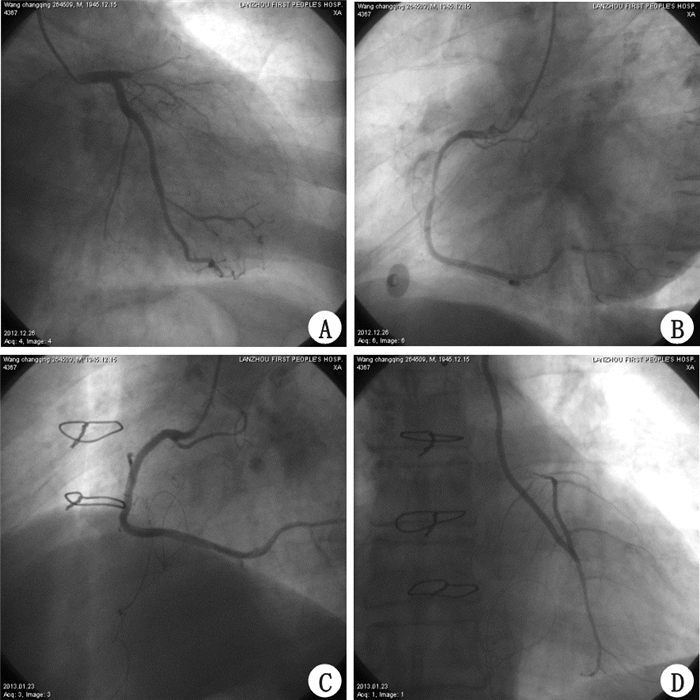

2 结 果6例接受6根移植物,均为LIMA原位移植。共植入支架8个。平均每例心肌血管化2.3支。主动脉内囊反搏泵(IABP)术前应用1例,术后应用2例。罪犯血管TIMI血流术前为0级,术后均为3级(图 1)。全组无死亡,围手术期心肌梗死、伤口感染等并发症。MIDCAB手术时间1.0~2.5 h,(1.5±0.4) h。术后脱机时间为2~12 h,(7.5±1.9) h。LIMA 血流量为38~110 mL/min,(45±15) mL/min。胸腔引流量为150~1100 mL(276±192)mL,输血率33.3% (2/6)。ICU 时间2.0~6.0 d,( 3.9± 0.6) d。术后住院8~15 d,平均12.0 d。6例随访0.5~7.0 年,( 2.6± 0.8)年,无远期死亡和心肌梗死。术后心功能NYHA分级Ⅰ级2例,Ⅱ级3例,Ⅲ级1例。术后冠脉造影4例,冠脉CT检查5例(图 2),乳内动脉均通畅良好,未发现支架内再狭窄。

| AMI前降支为罪犯血管100%狭窄,TIMI血流0级,PCI失败(A) AMI右冠脉第二段95%以上狭窄,TIMI血流1级(B) 先P CI右冠脉内植入支架 ,TIMI血流3级(C) 后MIDCAB, LIMA-LAD吻合,术后1周IMA造影LAD疏通,TIMI血流3级(D) 图 1 一站式心脏杂交手术术前及术后冠脉造影检查 |